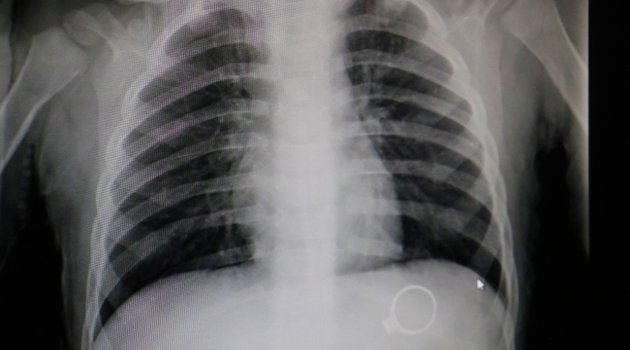

Sivas'ta kent merkezinde yaşayan F.G. ve C.G. çiftinin 1.5 yaşlarındaki M.G adındaki bebekleri oynamak için annesinden tek taş yüzüğünü istedi. Yüzükle oynayan M.G. annesine fark ettirmeden yüzüğü yuttu. Bir süre sonra çocuğunun yüzüğü yuttuğunu fark eden anne çocuğunu kucaklayarak Sivas Medicana Hastanesine götürdü. Burada Çocuk Cerrahisi Uzmanı Op.Dr. Mahmut Aluç tarafından muayene edildi. Yüzüğün, röntgeni çekilen M.G’nin midesinde olduğu görüldü. 6 gün sonra yüzük doğal yollarla çıktı. Çıkan yüzük aileye rahat bir nefes aldırdı.

Röntgende belli oldu

Çocuk Cerrahisi Uzmanı Op.Dr. Mahmut Aluç, çekilen röntgende yüzüğün midede olduğunu belirlediklerini ifade ederek, “Hastamız 1 buçuk yaşında. Bundan 6 gün önce bize yüzük yutma şikayeti ile başvurdu. İlk çektiğimiz grafide yüzüğün mide de olduğunu saptadık ve aileyi bilgilendirdikten sonra rutin prosedürlerinin gereği beklemeye başladık. 6 gün sonra spontane olarak yüzüğün kendisi çıktı. Bu tür hastalarla oldukça sık karşılaşıyoruz. Rutin olarak şöyle bir kural vardır, çocuk ağzına aldığı her şeyi yutabilir. Özellikle küçük çocuklar cisimleri tanımak için elleriyle dokunduktan sonra genellikle ağızlarına alırlar. Bu yutulan cisimler toplu iğne olabilir, çengelli iğne olabilir, para olabilir” dedi.